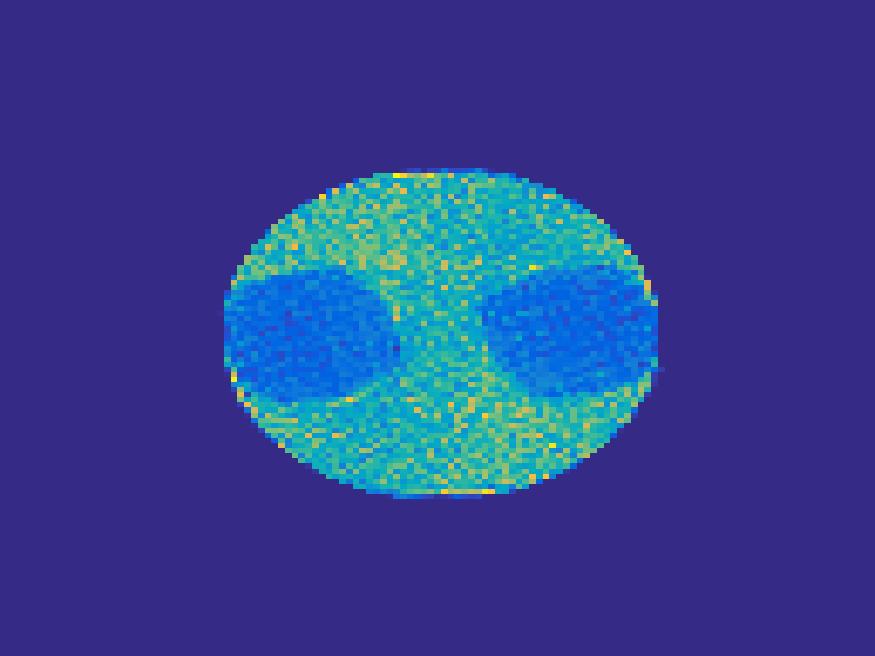

The proposed method is tested on numerical phantoms for a proof of concept study. We simulate image frames of size and projections per frame. Three time activity curves (TAC) for blood, liver and myocardium, previously used in [14] (see Figure 1), are used to simulate the dynamic images. The first simulated dynamic phantom is composed of two ellipses. In temporal direction, the positions of the two ellipses are stationary while the intensity in 90 frames within the region of each ellipse is generated according to the TAC of blood or liver. The projections are generated by using Radon transform sequentially performed for each frame.

In the tests, projections at two orthogonal angles are simulated for every frame to mimic 2-head camera data collection. The projection angles increase sequentially by along temporal direction. For example, at frame 1, projections are simulated at angle and , and at frame 2, angle and , etc. Finally, white Gaussian noise is added to the projection data. Reconstruction results with different methods are shown in Figure 3. Since the number of projections is very limited for each frame, the traditional FBP and least square methods cannot reconstruct the images satisfactorily, while the proposed method is capable to reconstruct the images effectively. Compared with SEMF model, when the edge of images jump (see frame 21 -frame 31 in Figure 3), the proposed model can better capture the change of the tendency of TAC.